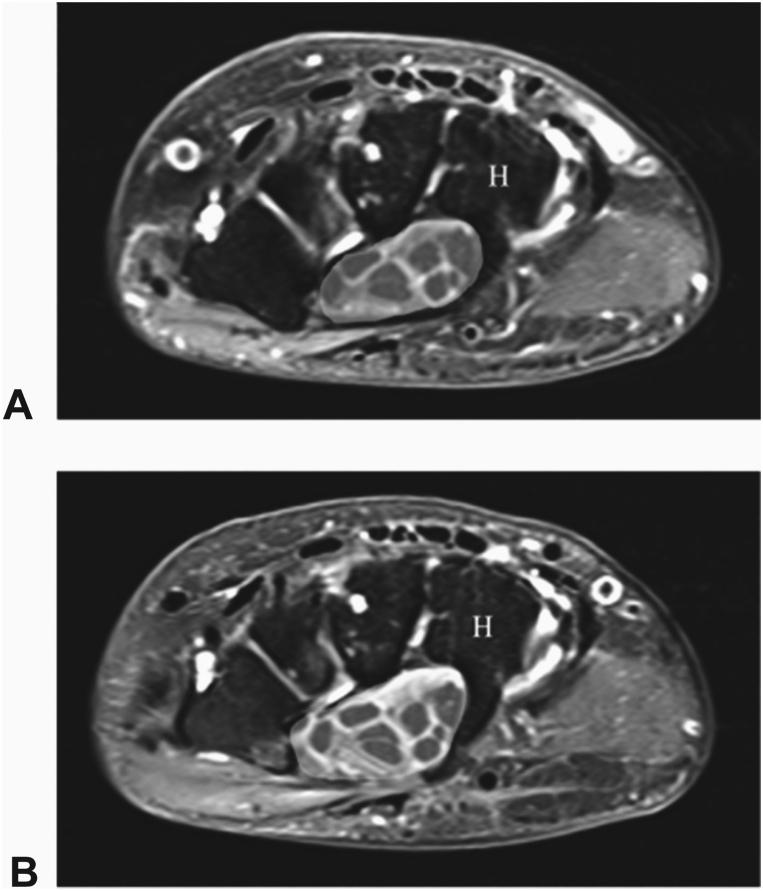

No complications were reported among 65 patients (68% women, 96 wrists). By 2 weeks, 97% of patients returned to normal activity and 100% returned to work. Statistically significant improvements in Boston Carpal Tunnel Questionnaire symptom severity scale, Boston Carpal Tunnel Questionnaire functional status scale, and Quick Disabilities of the Arm, Shoulder, and Hand scores occurred by the 2-week follow-up interval and persisted at 6 months (all < .001). Pre- and postoperative MRI scans were available for 13 patients (17 wrists) at the 3-month mean follow-up. Complete transverse carpal ligament transection was documented in all wrists. Key MRI findings included a 22% increase in carpal tunnel cross-sectional area at the hamate ( < .001), a 52% increase in median nerve cross-sectional area at the hamate ( < .001), an 18% reduction in median nerve signal intensity ( = .002), a 38% reduction in the flattening ratio of the median nerve at the hamate ( < .001), a 33% reduction in the flattening ratio of the median nerve at the pisiform ( < .001), a 20% reduction in the flattening ratio of the carpal tunnel at the hamate ( < .001), and a palmar shift of the median nerve relative to the hamate in all cases.

65例患者(68%为女性,共96侧腕关节)均未报告并发症。到术后2周时,97%的患者恢复了正常活动,100%的患者恢复了工作。在术后2周的随访时,波士顿腕管综合征问卷症状严重程度量表、波士顿腕管综合征问卷功能状态量表以及手臂、肩部和手部功能障碍快速评估量表评分均有统计学意义的改善,且在6个月时仍持续存在(均P <.001)。在平均3个月的随访时,13例患者(17侧腕关节)有术前和术后的MRI扫描资料。所有腕关节均记录到腕横韧带完全切断。MRI的主要发现包括:在钩骨处腕管横截面积增加22%(P <.001),在钩骨处正中神经横截面积增加52%(P <.001),正中神经信号强度降低18%(P = 0.002),在钩骨处正中神经扁平率降低38%(P <.001),在豌豆骨处正中神经扁平率降低33%(P <.001),在钩骨处腕管扁平率降低20%(P <.001),并且在所有病例中正中神经相对于钩骨向掌侧移位。